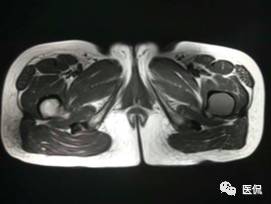

患者资料:男,26岁,左髋部疼痛10余天,无明显诱因出现左侧髋部疼痛,影像行走,夜间疼痛尤其明显。

影像资料:

(3)MRI ABC的特征为鼓囊状的膨胀性破坏,呈单囊或由低信号的间隔分隔成大小不等的多囊。因血细胞和血浆的分离和沉淀,囊内可见液-液平面。在T2WI上,液面上层为高信号,下层为低信号;T1WI上则相反,上层为低信号,下层为偏高信号。液-液平面是ABC较特征的征象。增强检查低信号的纤维间隔呈环形强化。继发性动脉瘤样骨囊肿可在其原发病灶内有液-液平。

【诊断要点】发生于青少年长骨干骺端偏心膨胀的溶骨性病变,MRI检查病灶内见有液-液平征象时应首先考虑为动脉瘤样骨囊肿。